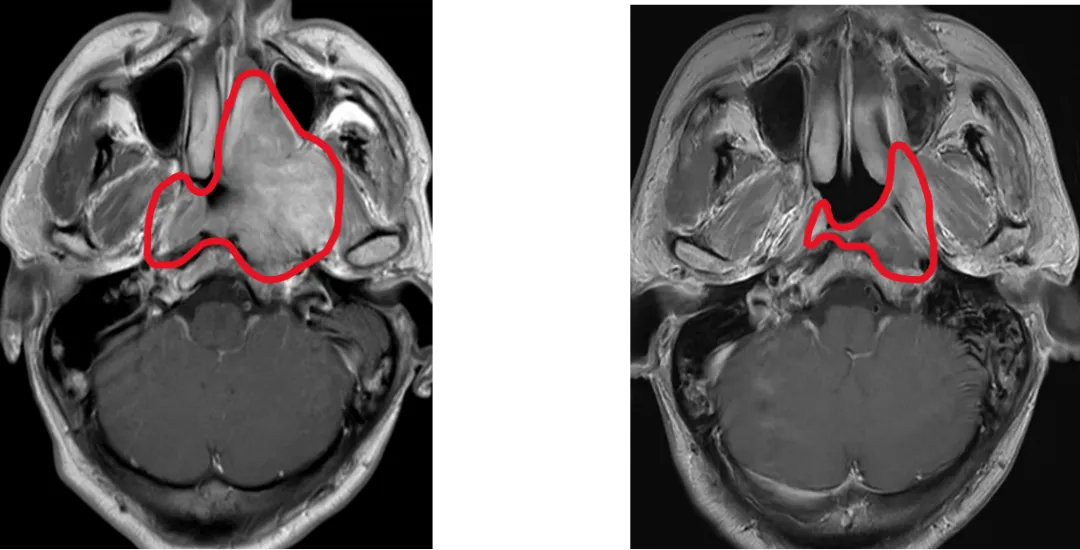

±ÇÑʰ©¸ß·¢ÓÚÖйú£¬£¬£¬Ð·¢²¡ÀýռȫÇò47%¡£·ÅÉäÖÎÁÆÊDZÇÑʰ©µÄ¸ùÖÎÊֶΣ¬£¬£¬µ«ÖÐÍíÆÚ»¼ÕßÐèÒªÔÚ·ÅÁÆÇ°½ÓÊÜ»¯ÁÆ£¬£¬£¬·ÅÁÆÇ°»¯ÁÆÊ¹90%»¼ÕßÖ×ÁöËõС£¬£¬£¬¶ø¼ÈÍù¹ú¼ÊÖ¸ÄÏÍÆ¼ö·ÅÁÆÕÕÉ乿ģÈÔÐè°üÀ¨»¯ÁÆÇ°Ö×Áö¾ÞϸÁýÕֵĹæÄ££¬£¬£¬µ¼ÖÂÖÜΧÕý³£×éÖ¯£¨ÈçÄÚ¶ú¡¢¡¢ÈùÏÙ£©½ÓÊܸ߼ÁÁ¿·øÉ䣬£¬£¬Òý·¢ÌýÁ¦ËðÉË¡¢¡¢¿Ú¸ÉµÈ²»¿ÉÄæ¸±×÷Ó㬣¬£¬ÑÏÖØÓ°Ï컼ÕßÉúÑÄÖÊÁ¿¡£

Ϊ´Ë£¬£¬£¬Âí¿¥ÔºÊ¿ÍŶÓÕö¿ªÓйØÑо¿£¬£¬£¬½ÓÄÉÁ˹ú¼ÊͨÓõıê×¼¶àÖÐÐÄ¡¢¡¢Ëæ»ú¡¢¡¢Æ½ÐбÈÕÕÉè¼Æ£¬£¬£¬ÄÉÈë445ÀýÖÐÍíÆÚ±ÇÑʰ©»¼Õߣ¬£¬£¬Ëæ»ú·ÖΪÁ½×飺»®·Ö»ùÓÚ»¯ÁƺóºÍ»¯ÁÆÇ°Ö×Áö¹æÄ£¾ÙÐзÅÁÆ¡£Ö÷ÒªÖÕµãΪ3Äê¾Ö²¿ÇøÓòÎÞ¸´±¬·¢ÑÄÂÊ£¬£¬£¬´ÎÒªÖÕµã°üÀ¨¶¾¸±·´Ó³ºÍÉúÑÄÖÊÁ¿¡£

ÕâÏî¶àÖÐÐÄIIIÆÚÁÙ´²ÊÔÑé֤ʵ£¬£¬£¬½öÕÕÉ仯ÁƺóµÄÖ×Áö¹æÄ££¬£¬£¬²¢Ã»ÓÐÔöÌí¸´·¢£¬£¬£¬È´ÏÔÖø½µµÍÁ˶¾¸±·´Ó³£¬£¬£¬ÏÔÖø¸ÄÉÆ»¼ÕßÉúÑÄÖÊÁ¿£¬£¬£¬Ê¹ÎÒ¹ú±ÇÑʰ©ÕïÁÆÊµÏÖ´Ó¡°±£ÉúÑÄ¡±µ½¡°ÓÅÉúÑÄ¡±µÄ¿çÔ½Ê½Í»ÆÆ¡£3Äê¾Ö²¿ÇøÓòÎÞ¸´±¬·¢ÑÄÂÊ´ï91.5%£¨Óë¹Å°åÁÆ·¨³Öƽ£©£»ÑÏÖØ·ÅÉäÐÔ¿ÚÇ»ð¤Ä¤Ñ×½µµÍ4³É£¬£¬£¬ÍíÆÚÑÏÖØÖжúÑ×±¬·¢ÂÊÈñ¼õ5³É£¬£¬£¬¿Ú¸ÉÖ¢×´¸ÄÉÆ6³É£»ÕûÌ念½¡×´Ì¬¡¢¡¢ÌåÁ¦×´Ì¬¡¢¡¢ÇéÐ÷¹¦Ð§ÏÔÖø¸ÄÉÆ£¬£¬£¬¿Ú¸É¼°ÍÙÒºð¤³íÖ¢×´¼õÇá¡£